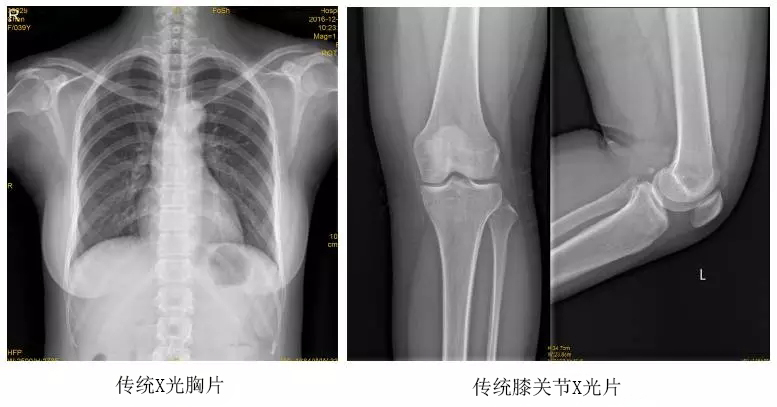

以某院所攝X光片為例,對比傳統(tǒng)攝片與全身拼接功能的區(qū)別:

傳統(tǒng)X光片只能觀察每個部位的局部情況,無法在統(tǒng)一體上進行連續(xù)、全面的觀察,全脊柱及下肢全長片則能直觀的看到整體形變。通過DR全身拼接功能實現(xiàn)的完整成像,為診治脊柱及下肢畸形提供了完美的臨床影像依據(jù),對臨床診斷、術(shù)前手術(shù)方案的制定和術(shù)后療效的評估等臨床應(yīng)用具有十分重要的意義,有效滿足了此類疾病臨床診斷和治療的要求。